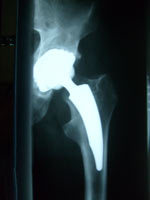

• Hüftgelenkverschleiß (Coxarthrose) oder Absterben des Hüftkopfes (Hüftkopfnekrose) führen zu einer schmerzhaften Einsteifung des Gelenkes. Bei der Operation werden Kopf und Pfanne ersetzt (Totalendoprothese). Der Anatomie und Knochenqualität entsprechend kommen dabei zur Anwendung: Schenkelhalsprothese, Kurzschaft oder Standardschaft, Langschaft oder zementierter Schaft. Als Gleitpaarung (Kopf/Pfanneninlay) kommen zum Einsatz: Keramik/Keramik, Keramik/Polyethylen, Metall/Polyethylen.

Kurzschaftprothese Kurzschaftprothese Sonderprothese Sonderprothese